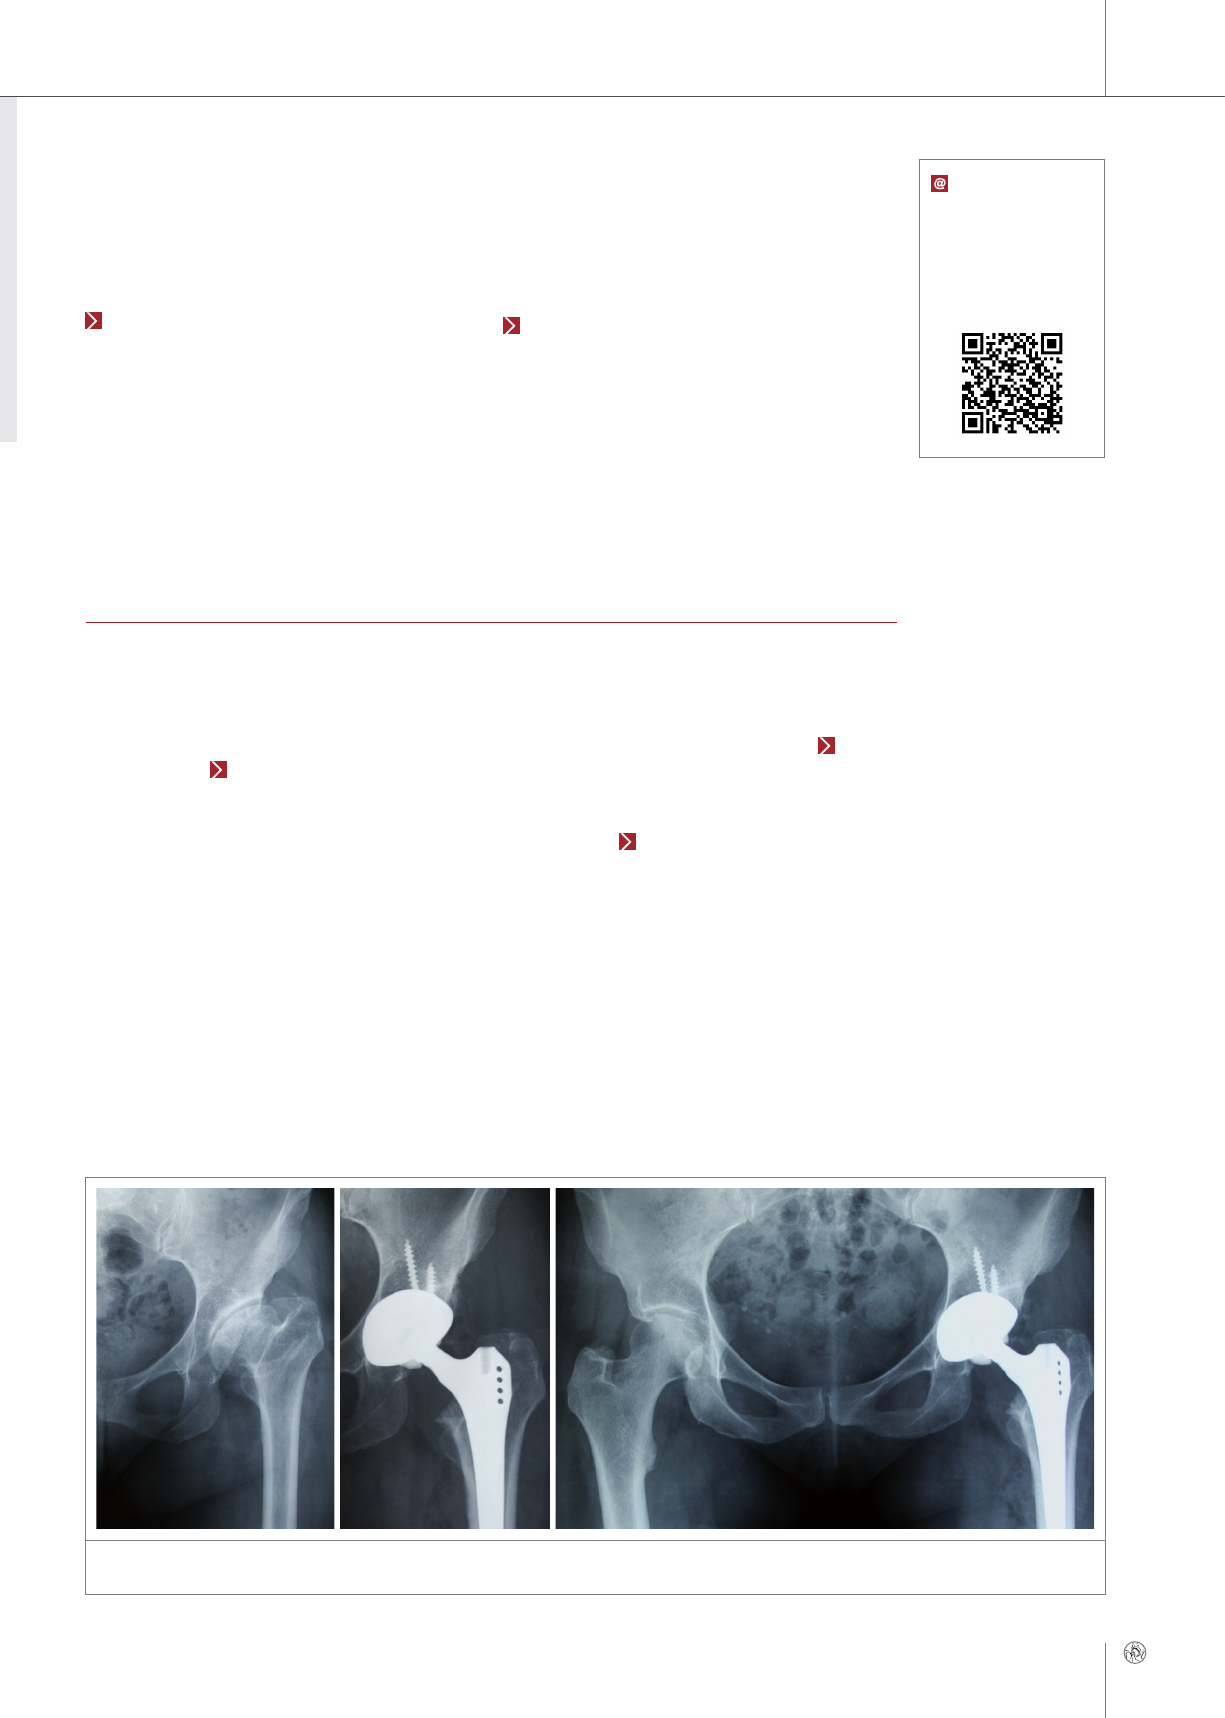

Mid-term Results of Modern Ceramic-on-Ceramic

Total Hip Arthroplasty

Laforgia R1, Pelone F2, Porporati AA3, Santovito L1, Piconi C4

1Mater Dei Hospital, Bari, Italy; 2Kingston University and St. George’s, University of London, London, Great

Britain; 3CeramTec GmbH, Plochingen, Germany; 4Catholic University, Orthopedics and Traumatology Ins-

titute, Rome, Italy

The use of CoC bearings in total hip arthroplasty is growing worldwide. Especially bearings larg-

er than 32 mm have been confirmed as a valid option for increased range of motion (RoM) and

stability combined with extremely low wear, and some authors are suggesting that this coupling

is the gold standard in hip arthroplasty. To characterize the outcomes of modern CoC bearings,

a retrospective study was performed on patients who underwent hip arthroplasty with alumina

composite in 3 clinical centers located in the Puglia region of Italy.

142 patients who underwent hip arthroplasty with

CoC bearings (Biolox®delta, CeramTec, Germany)

were enrolled in this study, carried out at 3 clinical

centers located in Puglia, Italy. Mean follow-up time

was 47.6 months (SD: 7.9; minimum 11.7, maxi-

mum: 68.4). Mean patients’ age was 68 (SD: 11;

minimum: 38, maximum: 86). 63 patients (44.4 %)

were male, and the mean BMI was 27.6 (SD: 4.2;

minimum: 18.8, maximum: 45.0).

74 bearings had a diameter of 36 mm (52.1%), and

55 bearings a diameter of 32 mm (38.7 %), while

bearings of 40 mm and 28 mm in diameter were im-

planted in eight (5.6 %) and five (3.5 %) cases, re-

spectively.